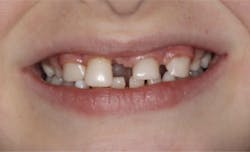

Upon clinical and radiographic examination, the patient presented with multiple missing permanent teeth (figures 3, 4a, and 4b). Tooth No. 8 was malpositioned and slightly mobile. Her mandibular dentition was stable and intact, although mostly deciduous (figure 5). Upon further questioning, I learned that her brother had a similar condition. Taking into consideration the patient’s physical appearance and the genetic similarity to her brother, I discussed with her parents the need to obtain a medical diagnosis through genetic testing.